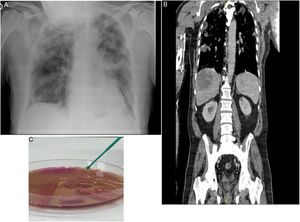

A: Radiografía de tórax al ingreso: infiltrados pulmonares bilaterales compatibles con bronconeumonía. B: TAC toracoabdominal, corte coronal mostrando absceso hepático e infiltrados pulmonares bilaterales. C: Placa agar MacConkey: crecimiento de colonias de Klebsiella pneumoniae hipermucoviscosa.

Varón de 70 años natural de Argelia y residente en España, sin haber viajado recientemente. Exfumador de 16 paquetes/año, diabético tipo 2, con cardiopatía isquémica crónica, sin antecedentes neumológicos, en tratamiento con atenolol, ramipril y metformina. Acudió a urgencias por fiebre de 3 días de evolución, asociado a náuseas y dolor pleurítico derecho. A la exploración presentaba regular estado general, se encontraba taquipneico con 22rpm, con O2 en cánulas nasales a 4l/min tenía una SaO2 de 95%, tensión arterial de 100/50mmHg, frecuencia cardiaca de 85lpm, encontrándose febril con una temperatura de 39°C. La auscultación pulmonar presentaba crepitantes hasta los campos medios bilaterales. Se le realizó una radiografía de tórax en la que se observaron infiltrados periféricos en ambos hemitórax, compatibles con bronconeumonía (fig. 1A).

En las pruebas complementarias de urgencias destacaba gasometría arterial (FiO2 0,21): pH 7,44; PaCO231mmHg, PaO253mmHg, HCO320,9mmol/l, PaO2/FiO2252; analítica con leucocitos 8.310/ml, neutrófilos 77%, linfocitos 8,1%; hematíes 4.100.000/ml; hemoglobina 12,2g/dl; hematocrito33%; plaquetas119.000/ml; índice de Quick 68%; dímero D 1.772ng/ml, glucosa 280mg/dl, urea 42mg/dl; creatinina1,46mg/dl; albúmina2,40g/dl; sodio 130mmol/l; potasio 3,50mmol/l; ALT143U/l; LDH281U/l; proteína C reactiva>25mg/dl. El sedimento de orina fue normal. La PCR de SARS CoV-2 fue negativa. A las 48horas los hemocultivos mostraron crecimiento de Klebsiella pneumoniae multisensible. El urocultivo y la antigenuria para Legionella y neumococo fueron negativos. A las 24horas el paciente presentó hipotensión, mayor taquipnea, Tª 38°C y empeoramiento radiológico, con infiltrados parcheados en progresión bilateral. En la TAC toracoabdominal destacaba derrame pleural bilateral asociado a múltiples infiltrados alveolares nodulares, patrón en empedrado en ambos ápex y segmentos anteriores de ambos lóbulos superiores con defectos de repleción en arterias pulmonares lobares bilaterales. Se observaban 2 lesiones focales heterogéneas compatibles con abscesos hepáticos, de 8,8×6,5cm y de 2cm, tromboembolismo pulmonar agudo periférico bilateral, sin signos de sobrecarga derecha, y émbolos sépticos (fig. 1B), ingresando en la UCI ante la mala evolución presentada. La ecocardioscopia mostró FEVI60% sin dilatación de cavidades derechas. Mediante ecografía Doppler de extremidades inferiores se descartó trombosis venosa profunda.

Se realizó punción y drenaje percutáneo del absceso hepático, aislando en el cultivo Klebsiella pneumoniae, serotipo capsular K1, fenotipo hipermucoviscoso, multisensible y resistente a ampicilina (fig. 1C). En la serología para virus Epstein-Barr, citomegalovirus y virus herpes simple 1 y 2 obtuvimos anticuerpos IgM negativos e IgG positivos, todo ello compatible con infección pasada previamente y descartando viremia aguda. La serología para sífilis, VIH, VHB y VHC resultó negativa.